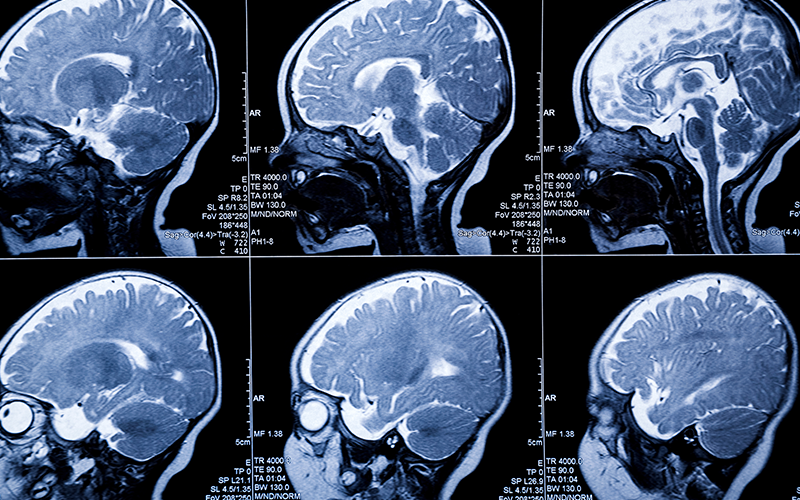

1 year baby MRI scan

When key nutrients are missing during this critical window, the effects can be lifelong—and in some cases, devastating. From neural tube defects and weakened immune systems to impaired brain development and rare neurological disorders like leukodystrophy, poor maternal nutrition doesn’t just leave a mark—it can alter the entire course of a child’s future.

From that moment onward, the transformation is breathtaking. By the age of one, a child’s brain reaches about 75% of its adult size. Every giggle, every bite, every cuddle triggers new neural pathways. Their immune system begins learning how to fight. Their bones stretch, organs mature, and tiny metabolic systems start making decisions that will influence weight, health, and even disease resistance for decades to come.